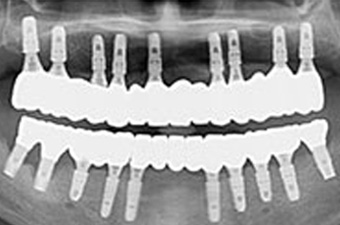

임플란트 보철

고정식 임플란트 보철

8개 이상의 임플란트를 식립하여 반영구적으로 사용이 가능하며 자연치아와 유사합니다.

단점 : 치과에 내원하여 보철물 청소해야함